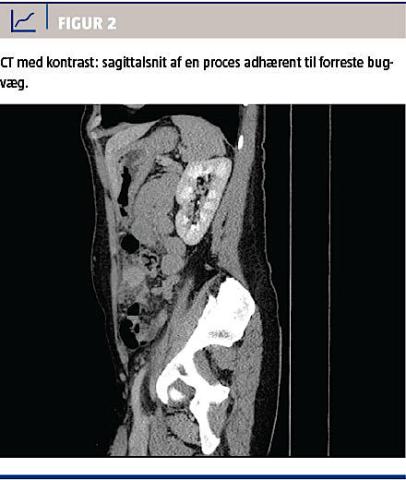

Ved en gynækologisk undersøgelse fandt man normale forhold med en spiral in situ. De vitale parametre var upåfaldende. En biokemisk undersøgelse viste normalt hæmoglobinniveau, basisk fosfatase og negativ S-humant choriongonadotropinniveau, men forhøjet C-reaktivt proteinniveau til 16 mg/l og alaninaminotransferaseniveau på 77 E/l. En CT af abdomen med i.v.-kontrast viste en atypisk inflammatorisk proces i venstre side af abdomen (Figur 1 og Figur 2), og der blev udført diagnostisk laparoskopi på mistanke om inflammeret Meckels divertikel. Ved laparoskopien fandt man i omentum majus en solid tumor, som var adhærent til forreste bugvæg. Efter at man havde sikret sig, at der i øvrigt var normale forhold intraabdominalt, blev tumoren laparoskopisk fjernet en bloc. Makroskopisk vurderet var tumoren 45 × 40 × 20 mm. På snitfladen var den fast heterogen med fedtvævslignende områder og nekroselignende forandringer centralt. Ved mikroskopi af omentet påvistes Actinomyces med karakteristiske sulphur granules bestående af bakterier og inflammatoriske celler (Figur 3). Dyrkning af ascitesvæske og podning fra IUD og cervix viste ingen vækst af Actinomyces. Efter konstatering af Actinomyces fik patienten fjernet spiralen og blev sat i i.v.-behandling med penicillin 5 mio. IE × 4 dagligt i 13 dage, efterfulgt af otte dages behandling med clindamycin 900 mg. Derefter blev patienten behandlet med amoxicillin 750 mg × 3 dagligt.